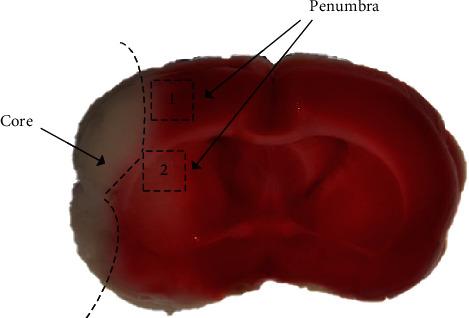

Microglia in the penumbra shifted from M2 to M1 phenotype between 3 and 5 days after cerebral ischemia-reperfusion, which promoted local inflammation and injury. Shaoyao-Gancao Decoction (SGD) has been found to result in a significant upregulation of IL-13 in the penumbra, which has been shown to induce polarization of M2 microglia. There was thus a hypothesis that SGD could exert an anti-inflammatory and neuroprotective effect by activating IL-13 to induce microglia polarization towards M2 phenotype, and the purpose of this study was to explore the influence of SGD on microglia phenotype switching and its possible mechanism. Rats who received middle cerebral artery occlusion surgery (MCAO) were treated with SGD for 3 or 6 days, to investigate the therapeutic effect and the underlying mechanism of SGD for cerebral ischemia-reperfusion injury (CI/RP). The results indicated that SGD improved neurobehavioral scores and reduced apoptosis. Furthermore, SGD significantly decreased M1 microglia and M1-like markers, but increased M2 microglia and M2 markers. Moreover, higher levels of IL-13 and ratios of p-JAK2/JAK2 and p-STAT6/STAT6 were found in the SGD group compared to the MCAO. In conclusion, it was verified that SGD prevented injury by driving microglia phenotypic switching from M1 to M2, probably via IL-13 and its downstream JAK2-STAT6 pathway. Given that no further validation tests were included in this study, it is necessary to conduct more experiments to confirm the reliability of the above results.